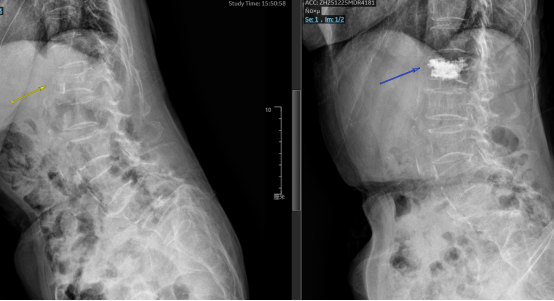

术前术后影像学检查对比显示:椎体高度完美恢复,骨水泥填充满意!